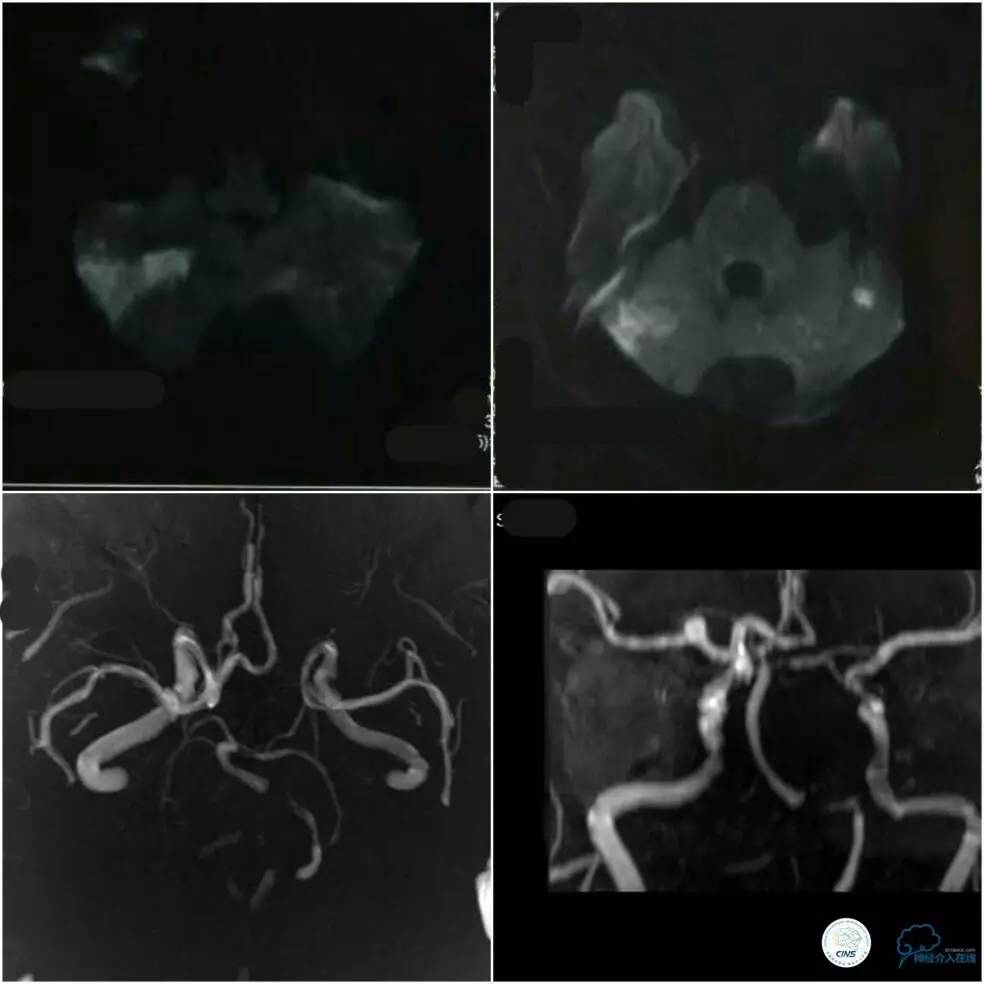

复查头MRI提示小脑、脑干及丘脑新发脑梗死病灶(图3),MRA提示双椎动脉末端及基底动脉中下段显影浅淡,双后交通动脉开放,右颈内动脉后交通段及右侧大脑中动脉M1段动脉瘤(图3)。

图3